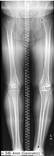

Leg length AI

Automatic measurement of leg lengths and angles. Limited generalizability.

N. Larson, C. Nguyen, BH. Do, et al.

Larson N, Nguyen C, Do B, Kaul A, Larson A, Wang S, Wang E, Bultman E, Stevens K, Pai J, Ha A, Boutin R, Fredericson M, Do L, Fang C. Artificial Intelligence System for Automatic Quantitative Analysis and Radiology Reporting of Leg Length Radiographs. J Digit Imaging. 2022 Dec;35(6):1494-1505. doi: 10.1007/s10278-022-00671-2. Epub 2022 Jul 6. PMID: 35794502; PMCID: PMC9261153.